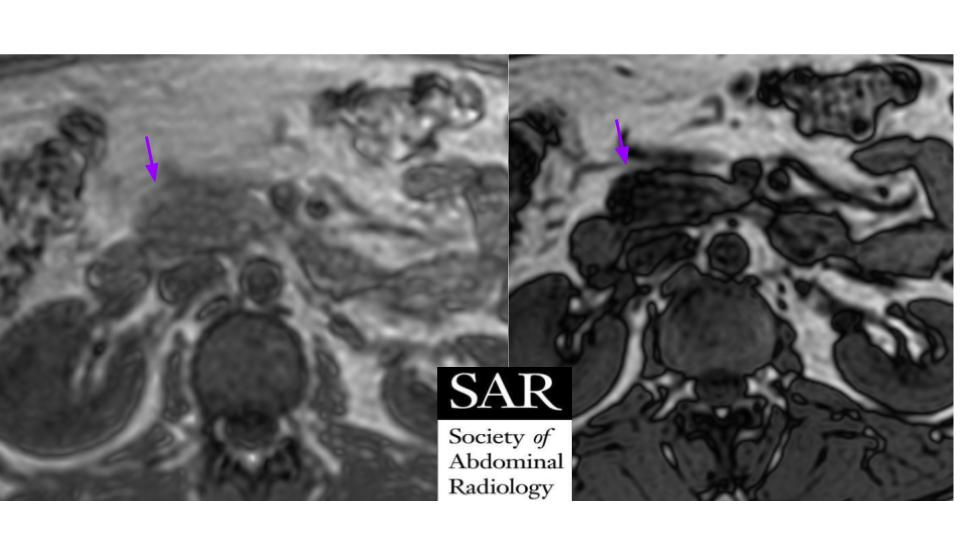

The answer for last week's case is: Paroxysmal nocturnal hemoglobinuria (MRI finding is hemosiderosis in the renal cortex seen here on T1 in phase image). Thanks for playing! Wait for a new challenge tomorrowpic.twitter.com/EDpdYuc1jr